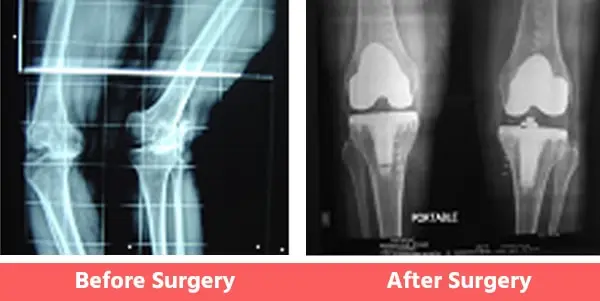

People may have certain deformities of the knee which include bow legs (varus), knock knees (valgus), or even wind-swept legs.

In such cases, the surgeon has to be well-experienced in handling such cases and should also have had considerable experience with revision joint replacement surgeries as well. See below Images.

3. Wind Swept Legs

Some Common Deformities

You can see illustration and X-Ray images shown above already.